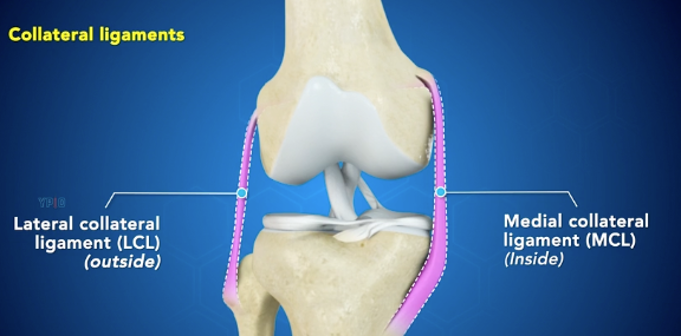

Oldal szalagok:

Oldal szalagok megakadályozzák a térd oldal irányú és hátrafelé történő túlfeszítését, túlnyúlását.

- Felületes belső oldalszalag (MCL-mediális oldalszalag) köti össze a combcsont és a sípcsont belső tapadási pontjait és ellentart külső irányú oldalsó (valgus) erőknek

- Mély belső oldalszalag (MCL-mediális oldalszalag) köti össze a combcsont belső részét és a mediális meniszkuszt

- Külső oldalszalag (LCL-külső oldalszalag) teljesen elkülönül az ízületi toktól és a combcsont külső részét köti össze a szárkapocscsonttal. Stabilizálja az ízületet és ellentart a belső oldalról eredő (varus) erőhatásoknak.